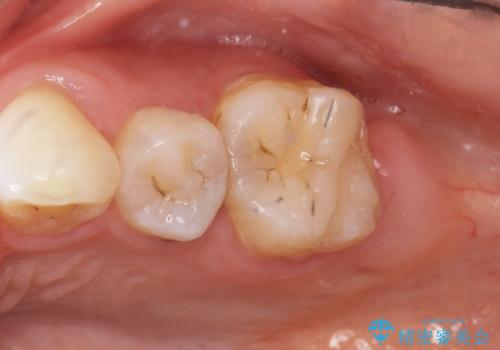

フロスを通すと臭い 歯と歯の間の虫歯 セラミックインレー 30代女性

- 歯と歯の間の虫歯治療を希望された患者様です。

フロスを通すと臭いのが気になるとの事でした。

精査したところ、左上の奥歯の間(左上56間)にう蝕を認めました。

う蝕を丁寧に除去したのち、セラミックインレーによる修復を行いました。